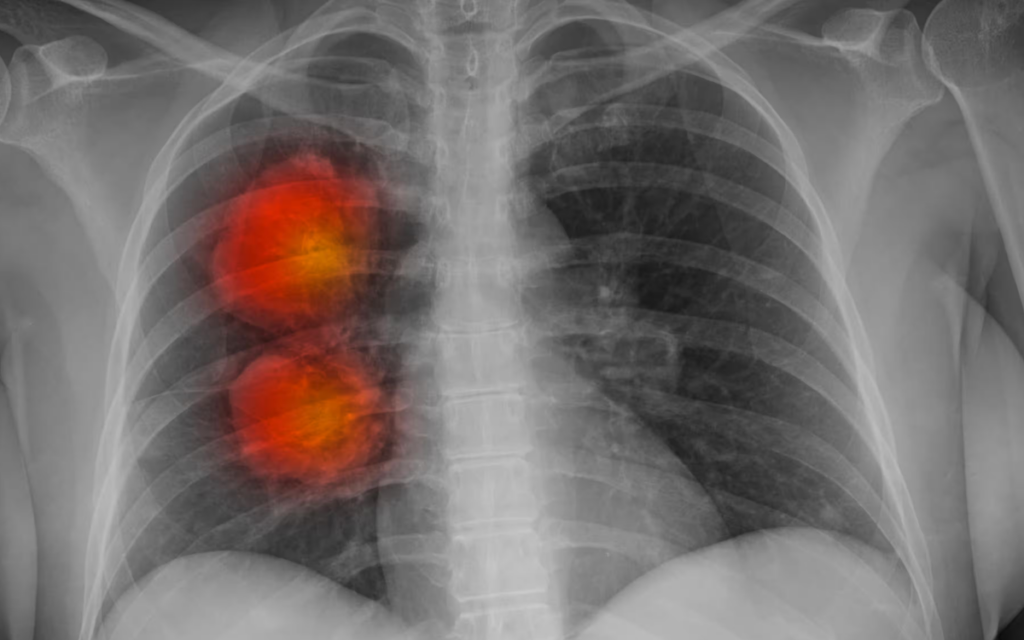

En algunos casos, el ADN puede desprenderse de los cromosomas y quedar separado dentro del núcleo, un fenómeno poco frecuente que antes se consideraba insignificante en el desarrollo del cáncer. Sin embargo, en una serie de tres artículos publicados por una coalición de investigadores de Estados Unidos y el Reino Unido, se descubrió que estos fragmentos de ADNec estaban presentes en las células tumorales de algunos de los cánceres más agresivos y resistentes al tratamiento.

«Esto no es solo un descubrimiento sobre lo que puede hacer que el cáncer sea tan malo, en realidad está señalando el camino hacia un nuevo conjunto de terapias«, afirma Paul Mischel, profesor de patología en la Universidad de Stanford. «Hay un camino a seguir para desarrollar nuevos tratamientos porque este tipo de ADN es diferente y crea vulnerabilidades que son diferentes».

Los fragmentos de ADNec, encontrados en el 17,1% de todos los tumores examinados en los estudios, portaban genes que impulsan el cáncer y otros genes que suprimen el sistema inmunológico. Los estudios también descubrieron que el ADNec puede replicarse (de manera caótica) y que esto también impulsa el crecimiento del cáncer.

Se descubrió que las células tumorales contenían muchos más fragmentos de ADNec que otras. Esto significa que una vez separadas de la estructura ADN-histona-cromosoma, no se dividen de manera uniforme junto con la célula. Algunas células hijas heredan mucho más ADNec que otras.